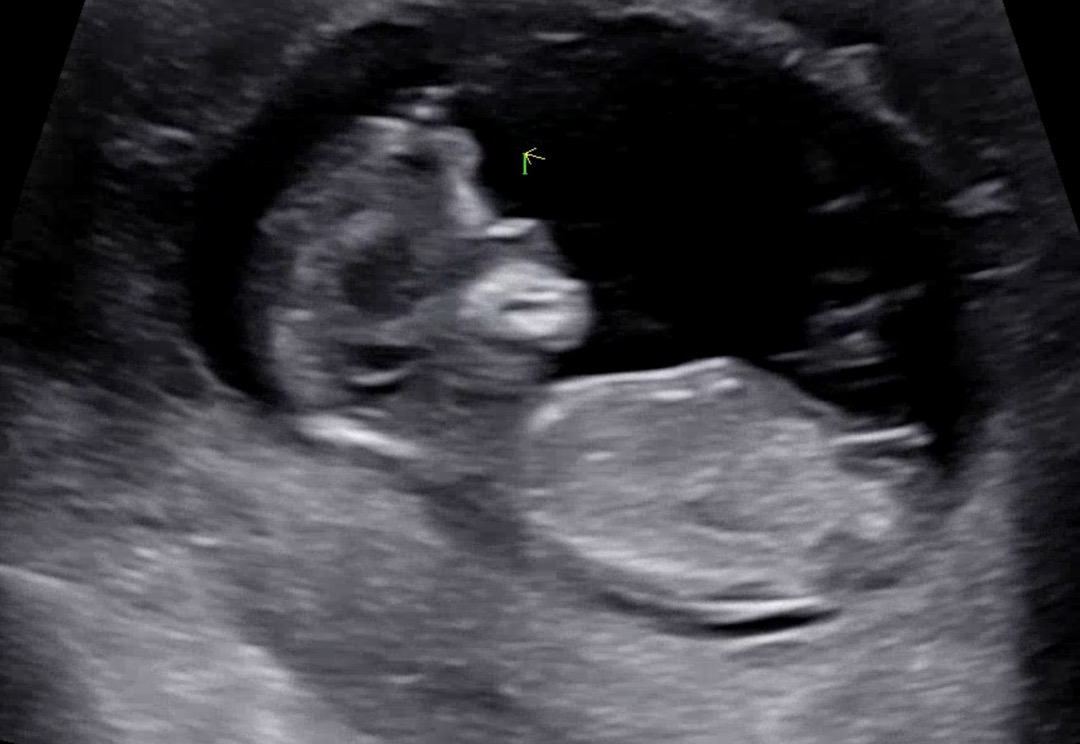

12주 0일차 각도법 봐주세요🙏🏻

성별 궁금해용😊